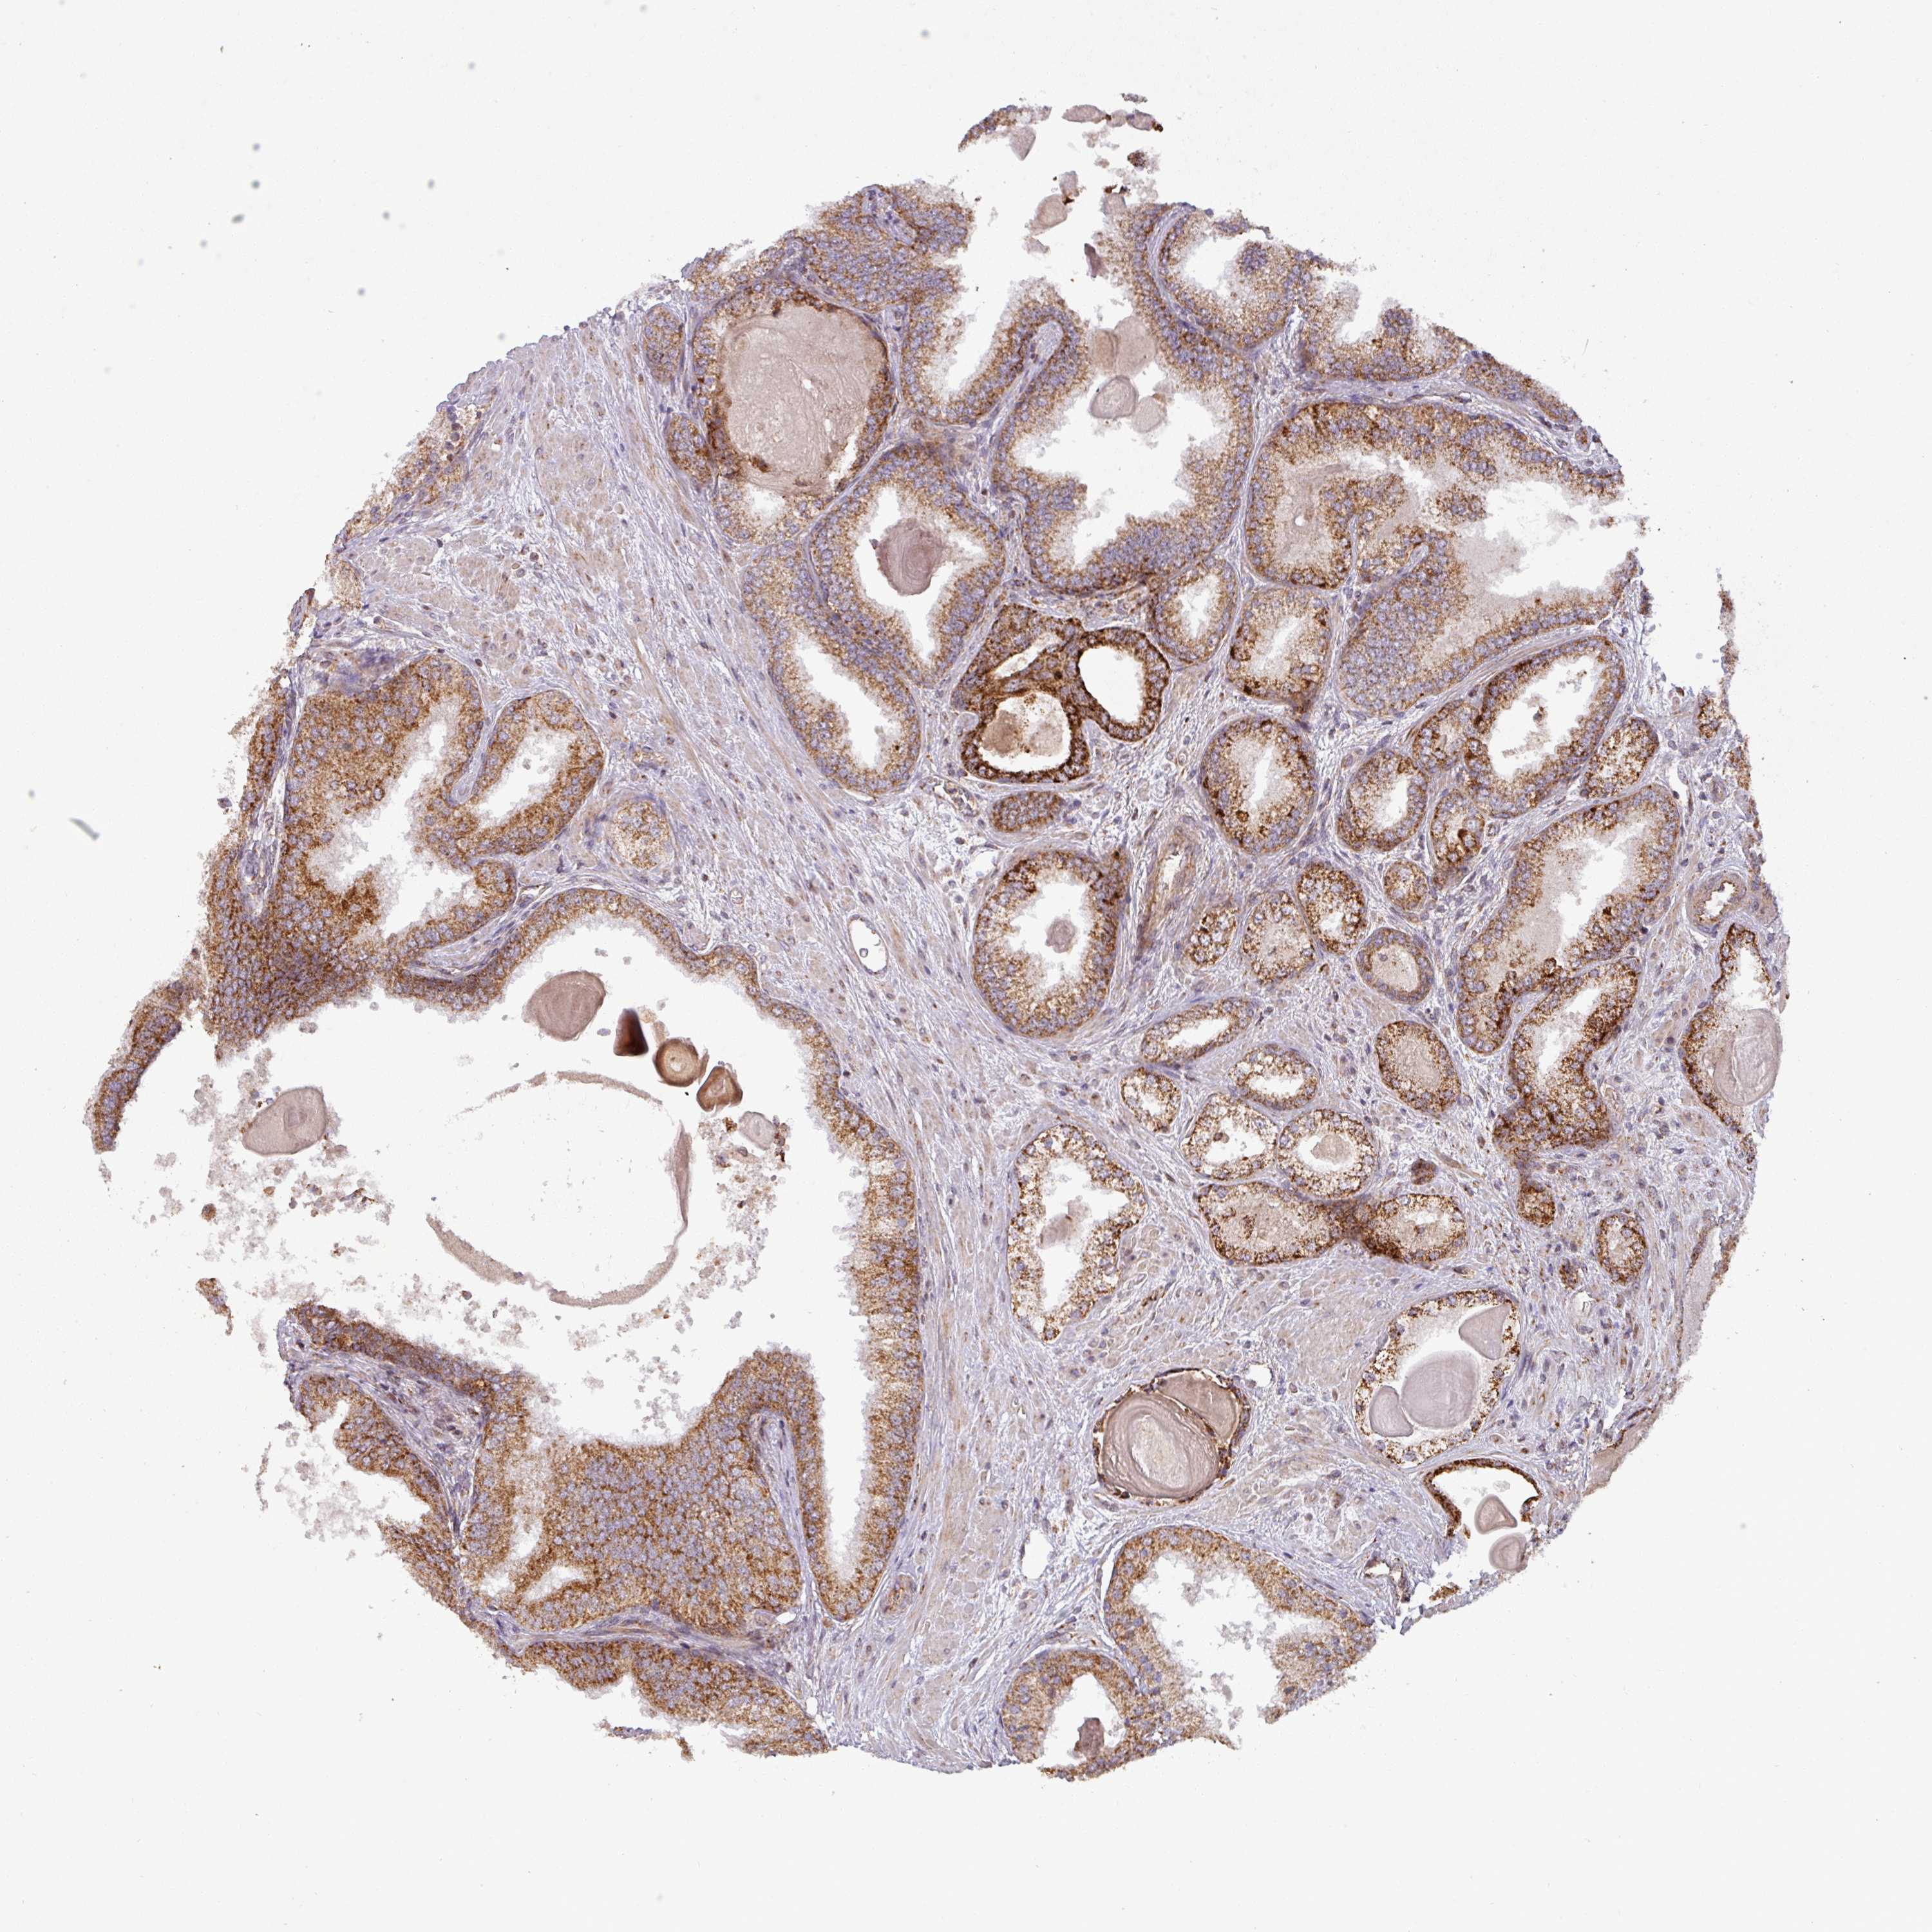

PROSTATE CANCER - Protein expressioni

A mouse-over function shows sample information and annotation data. Click on an image to view it in a full screen mode. Samples can be filtered based on level of antibody staining by selecting one or several of the following categories: high, medium, low and not detected. The assay and annotation is described here.

Note that samples used for immunohistochemistry by the Human Protein Atlas do not correspond to samples in the TCGA dataset.

Antibody stainingi

Antibody staining in the annotated cell types in the current human tissue is reported as not detected, low, medium, or high, based on conventional immunohistochemistry profiling in selected tissues. This score is based on the combination of the staining intensity and fraction of stained cells.

Each image is clickable and will lead to virtual microscopy that enables deeper exploration of all samples and also displays staining intensity scores, fraction scores and subcellular localization as well as patient and tissue information for each sample.

Antibody HPA008012

Antibody HPA045506

Staining

High

Medium

Low

Not detected

Intensity

Strong

Moderate

Weak

Negative

Quantity

>75%

75%-25%

<25%

None

Location

Nuclear

Cytoplasmic/membranous

Cytoplasmic/membranous,nuclear

Adenocarcinoma, Low grade

Adenocarcinoma, High grade